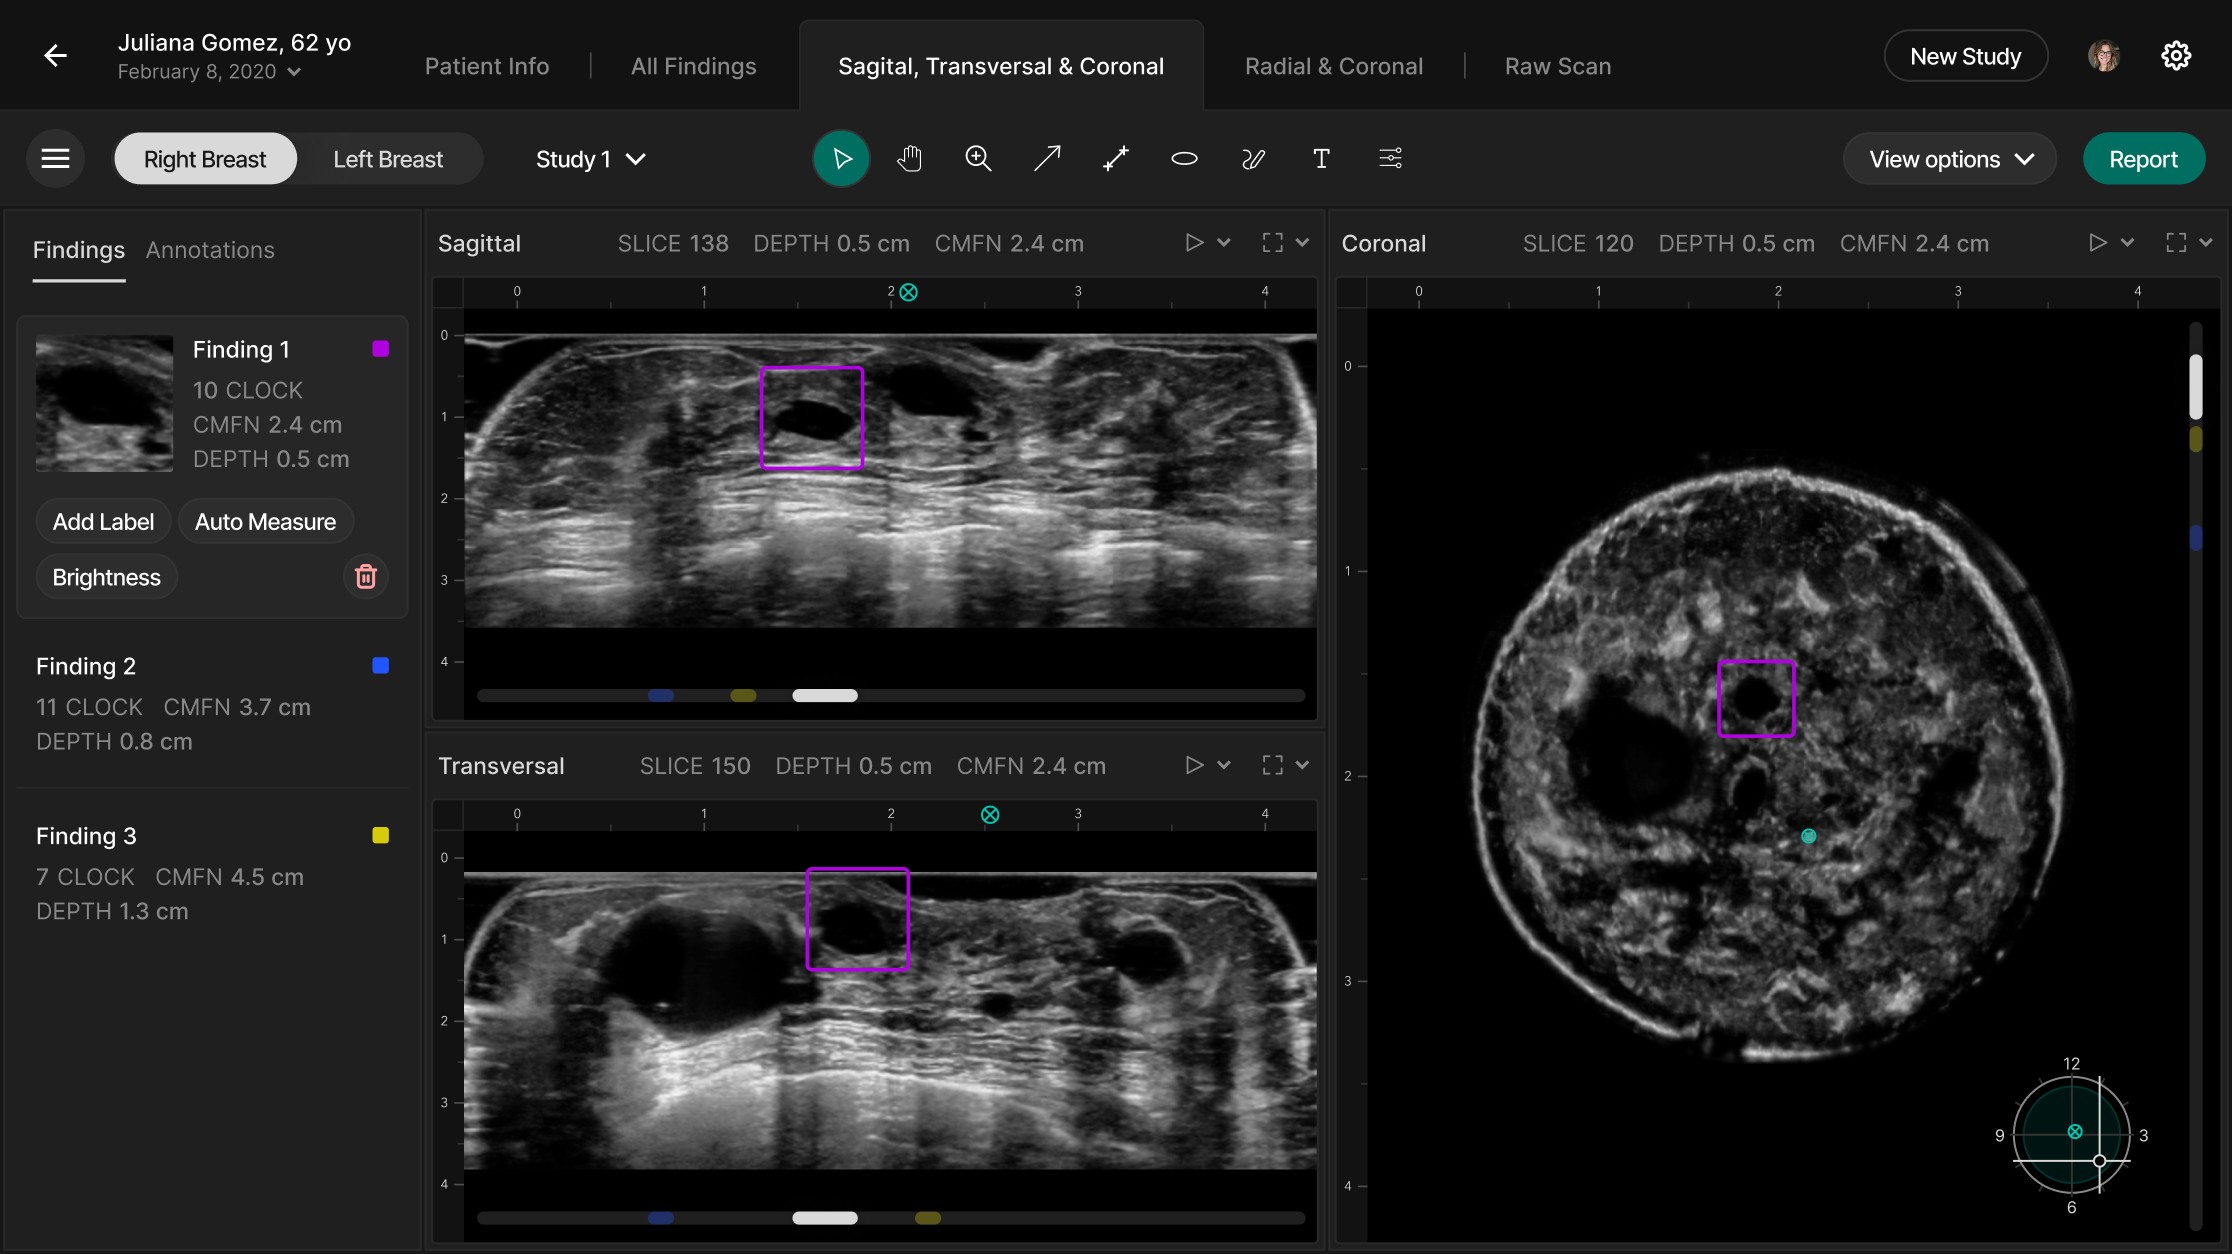

In UX/UI, we redesigned the review interface to surface only the most relevant 3D images (those flagged by AI), with an option to expand into a multi-plane comparison mode. The redesigned Scrubber allows radiologists to navigate slices quickly and correlate findings across planes, improving interpretation speed and clarity.

We streamlined the workflow by reducing clicks and removing friction, enabling doctors to access critical 3D images and AI-marked insights faster. This helped them more quickly distinguish between easy and complex cases, significantly reducing time spent per review.

Refined the Radiologist Experience

Designed a new interface that surfaces AI-flagged 3D images first, reducing the number of slices to review and easing cognitive load.